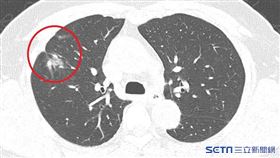

揪肺癌「這檢查」免費!2年找出1401個案

據統計肺癌為我國癌症死亡人數第1位,10348人也佔...

肺癌18年死亡率第1「2族群」為高風險

肺癌連續18年位居台灣癌症死亡第一名,患者存活率較低...